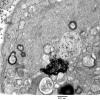

PERIPHERAL NEUROPATHY

4 AXONAL DEGENERATION

3 Electron Microscopy (2)